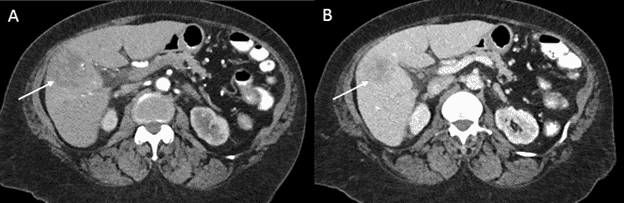

Наприклад, Rayar та ін. повідомили про дослідження з 45 пацієнтів, що мали неоперабельну вХАК, та проходили комбіновану Y-90 радіоемболізацію із системною хіміотерапією, та продемонстрували хороші результати, включаючи перехід до резектабельності у 8 пацієнтів.[27]

Зобр. 3. Репрезентативний приклад вХАК a) до та b) після радіоемболізації y-90

HAI також може використовуватися в поєднанні з системною хіміотерапією, як паліативне лікування або з метою зниження стадії процесу. У великому дослідженні ефективності HAI при вХАК, у 8 із 104 пацієнтів із неоперабельним раком було успішно знижено стадію процесу після терапії флоксуридином (при HAI) та системної хіміотерапії. Ці пацієнти зрештою пройшли резекцію, та мали медіану загальної виживаності 37 місяців.[28]